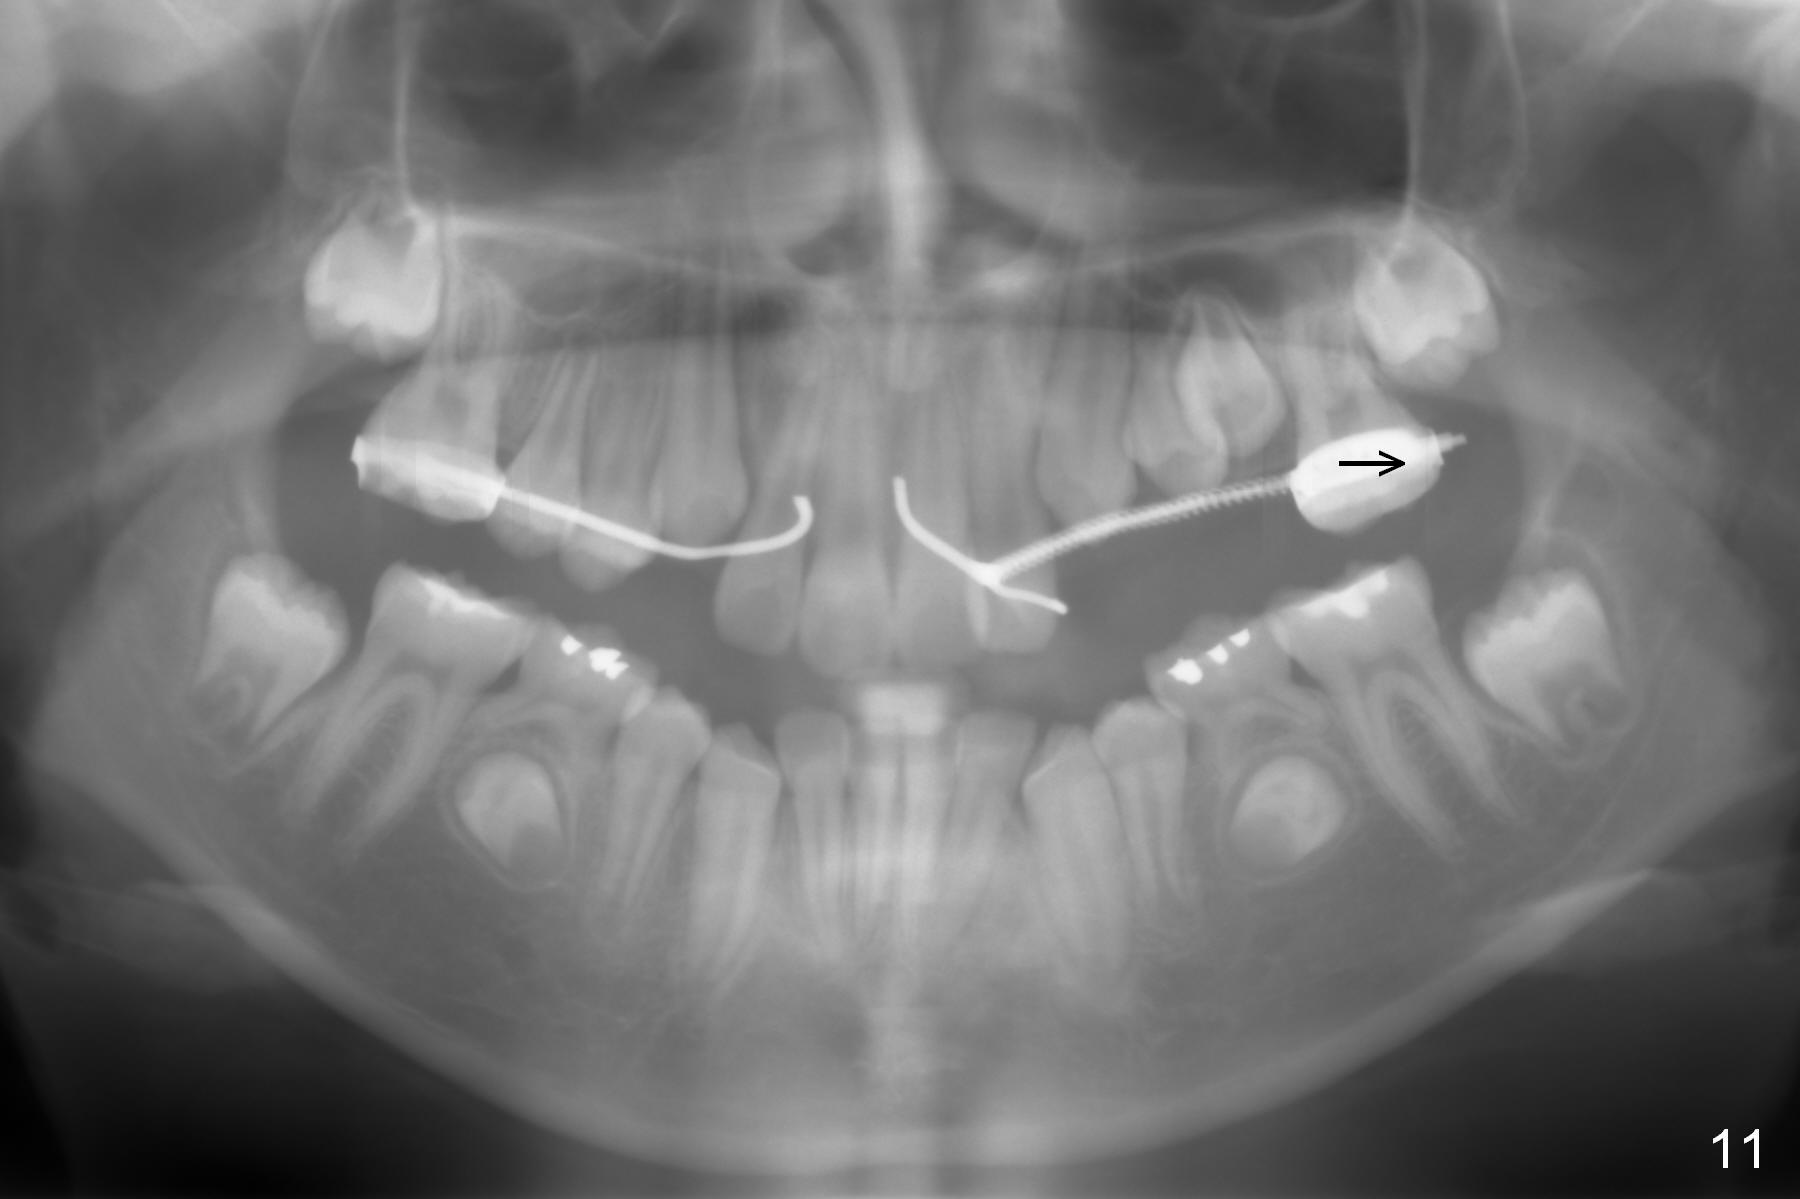

Nearly 2 months post regainer placement, UL6 appears to have been distalized (Fig.11 arrow), but UL4,5 have not erupted (Fig.12), while UL1,2 are displaced (Fig.13). Diode laser is used to expose the tooth buds, which are deeply seated (Fig.14). If they do not erupt soon, a mini implant should be placed for anchorage (Fig.10). Use several power chains to retract the anterior arm, while drill through the Nance appliance (high speed handpiece) for mini implant placement.